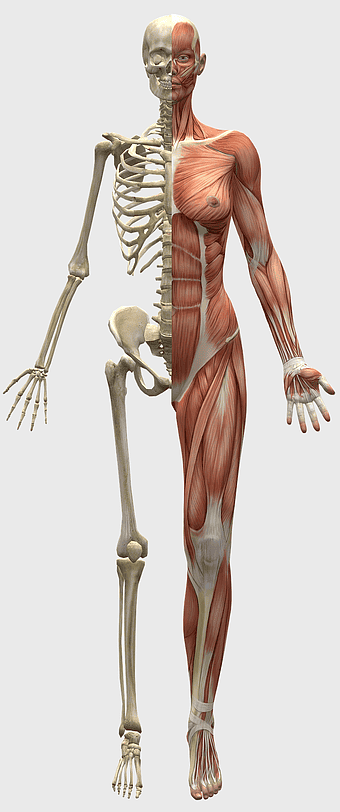

2210x3601px